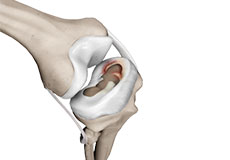

The knee is a hinge joint made up of two bones, the thighbone (femur) and shinbone (tibia). There are two round knobs at the end of the femur called femoral condyles that articulate with the flat surface of the tibia called the tibial plateau. The tibial plateau on the inside of the leg is called the medial tibial plateau and on the outside of the leg, the lateral tibial plateau.

The two femoral condyles form a groove on the front (anterior) side of the knee called the patellofemoral groove. A small bone called the patella sits in this groove and forms the kneecap. It acts as a shield and protects the knee joint from direct trauma.

Movement of the bones causes friction between the articulating surfaces. To reduce this friction, all articulating surfaces involved in the movement are covered with a white, shiny, slippery layer called articular cartilage. The articulating surface of the femoral condyles, tibial plateaus and the back of the patella are covered with this cartilage. The cartilage provides a smooth surface that facilitates easy movement.

Within the knee joint, between the femur and tibia, are two C-shaped cartilaginous structures called menisci. Menisci function to provide stability to the knee by spreading the weight of the upper body across the whole surface of the tibial plateau. The menisci help in load-bearing i.e. it prevents the weight from concentrating onto a small area, which could damage the articular cartilage. The menisci also act as a cushion between the femur and tibia by absorbing the shock produced by activities such as walking, running and jumping.